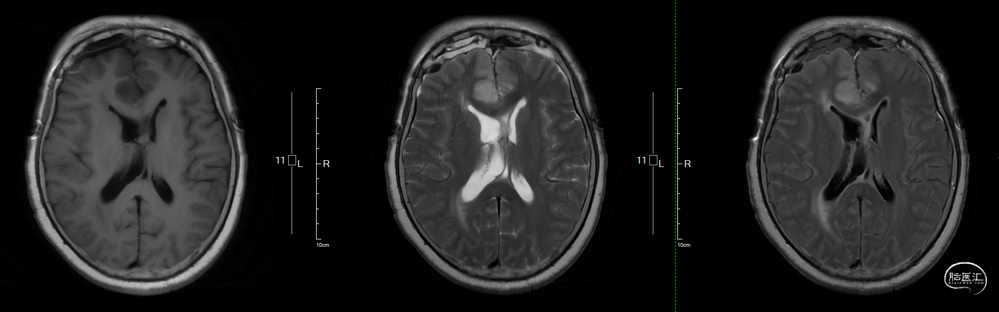

术后影像学

![]()

头部MRI提示:影像学全切,脑积水得到明显好转,实性部分未见显影,垂体组织保留良好。